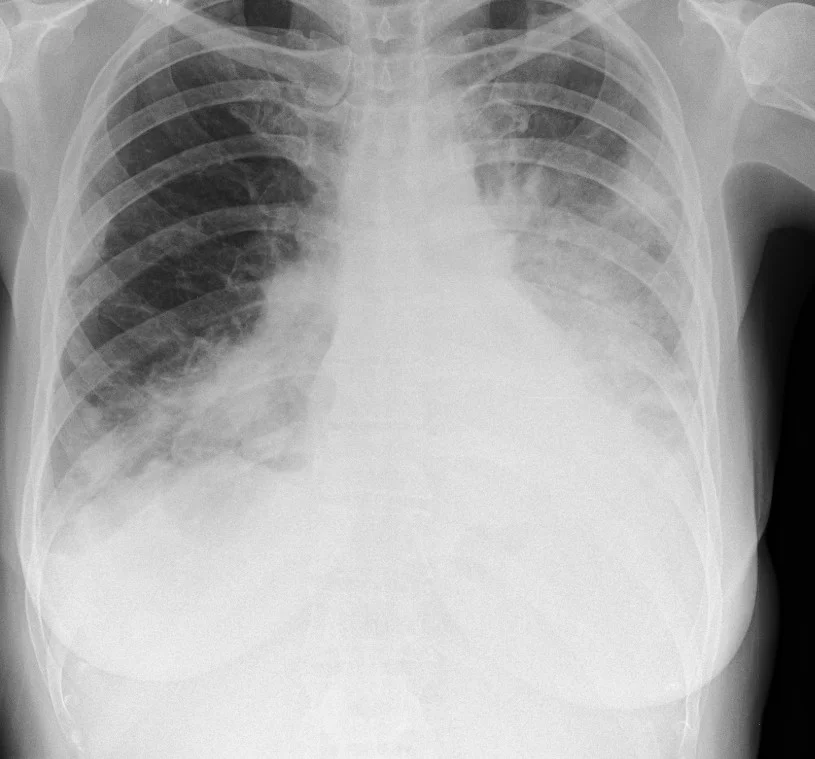

Extensive coverage of practically all possible radiograph presentations of both common and rare conditions in Chest, Abdominal and Musculoskeletal radiology have been included.

Classical Chest signs included:

Numerous chest illnesses and disorders also covered:

Master your FRCR 2B examination with authentic, expert-created content. Access 1,250+ short cases (2,000+ radiographs) across 50 packets, plus 600+ long cases (1,000+ cross-sectional images) in 100 packets. Every image is a full lossless DICOM at diagnostic workstation quality, following RCR display guidelines. No AI-generated content – all cases, questions, and answers are meticulously crafted by experienced radiologists.

Experience authentic FRCR 2B preparation with our professional DICOM viewer displaying full lossless images at diagnostic workstation quality. Access 1,250+ short cases and 600+ long cases – all created by expert radiologists with zero AI-generated content.

2,000+ radiographs and 1,000+ cross-sectional images in full lossless DICOM format.

Zero AI content – all cases created by expert consultant radiologists.